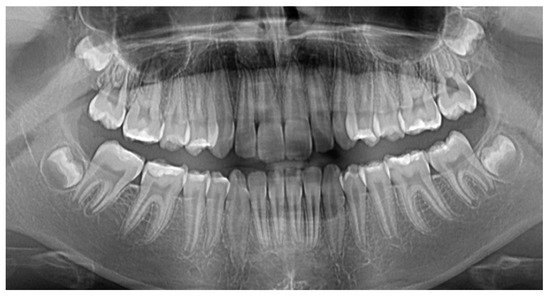

The Combination of Diode Laser and Ozonated Water in the Treatment of Complicated Pulp Gangrene

2.1. Study Participant